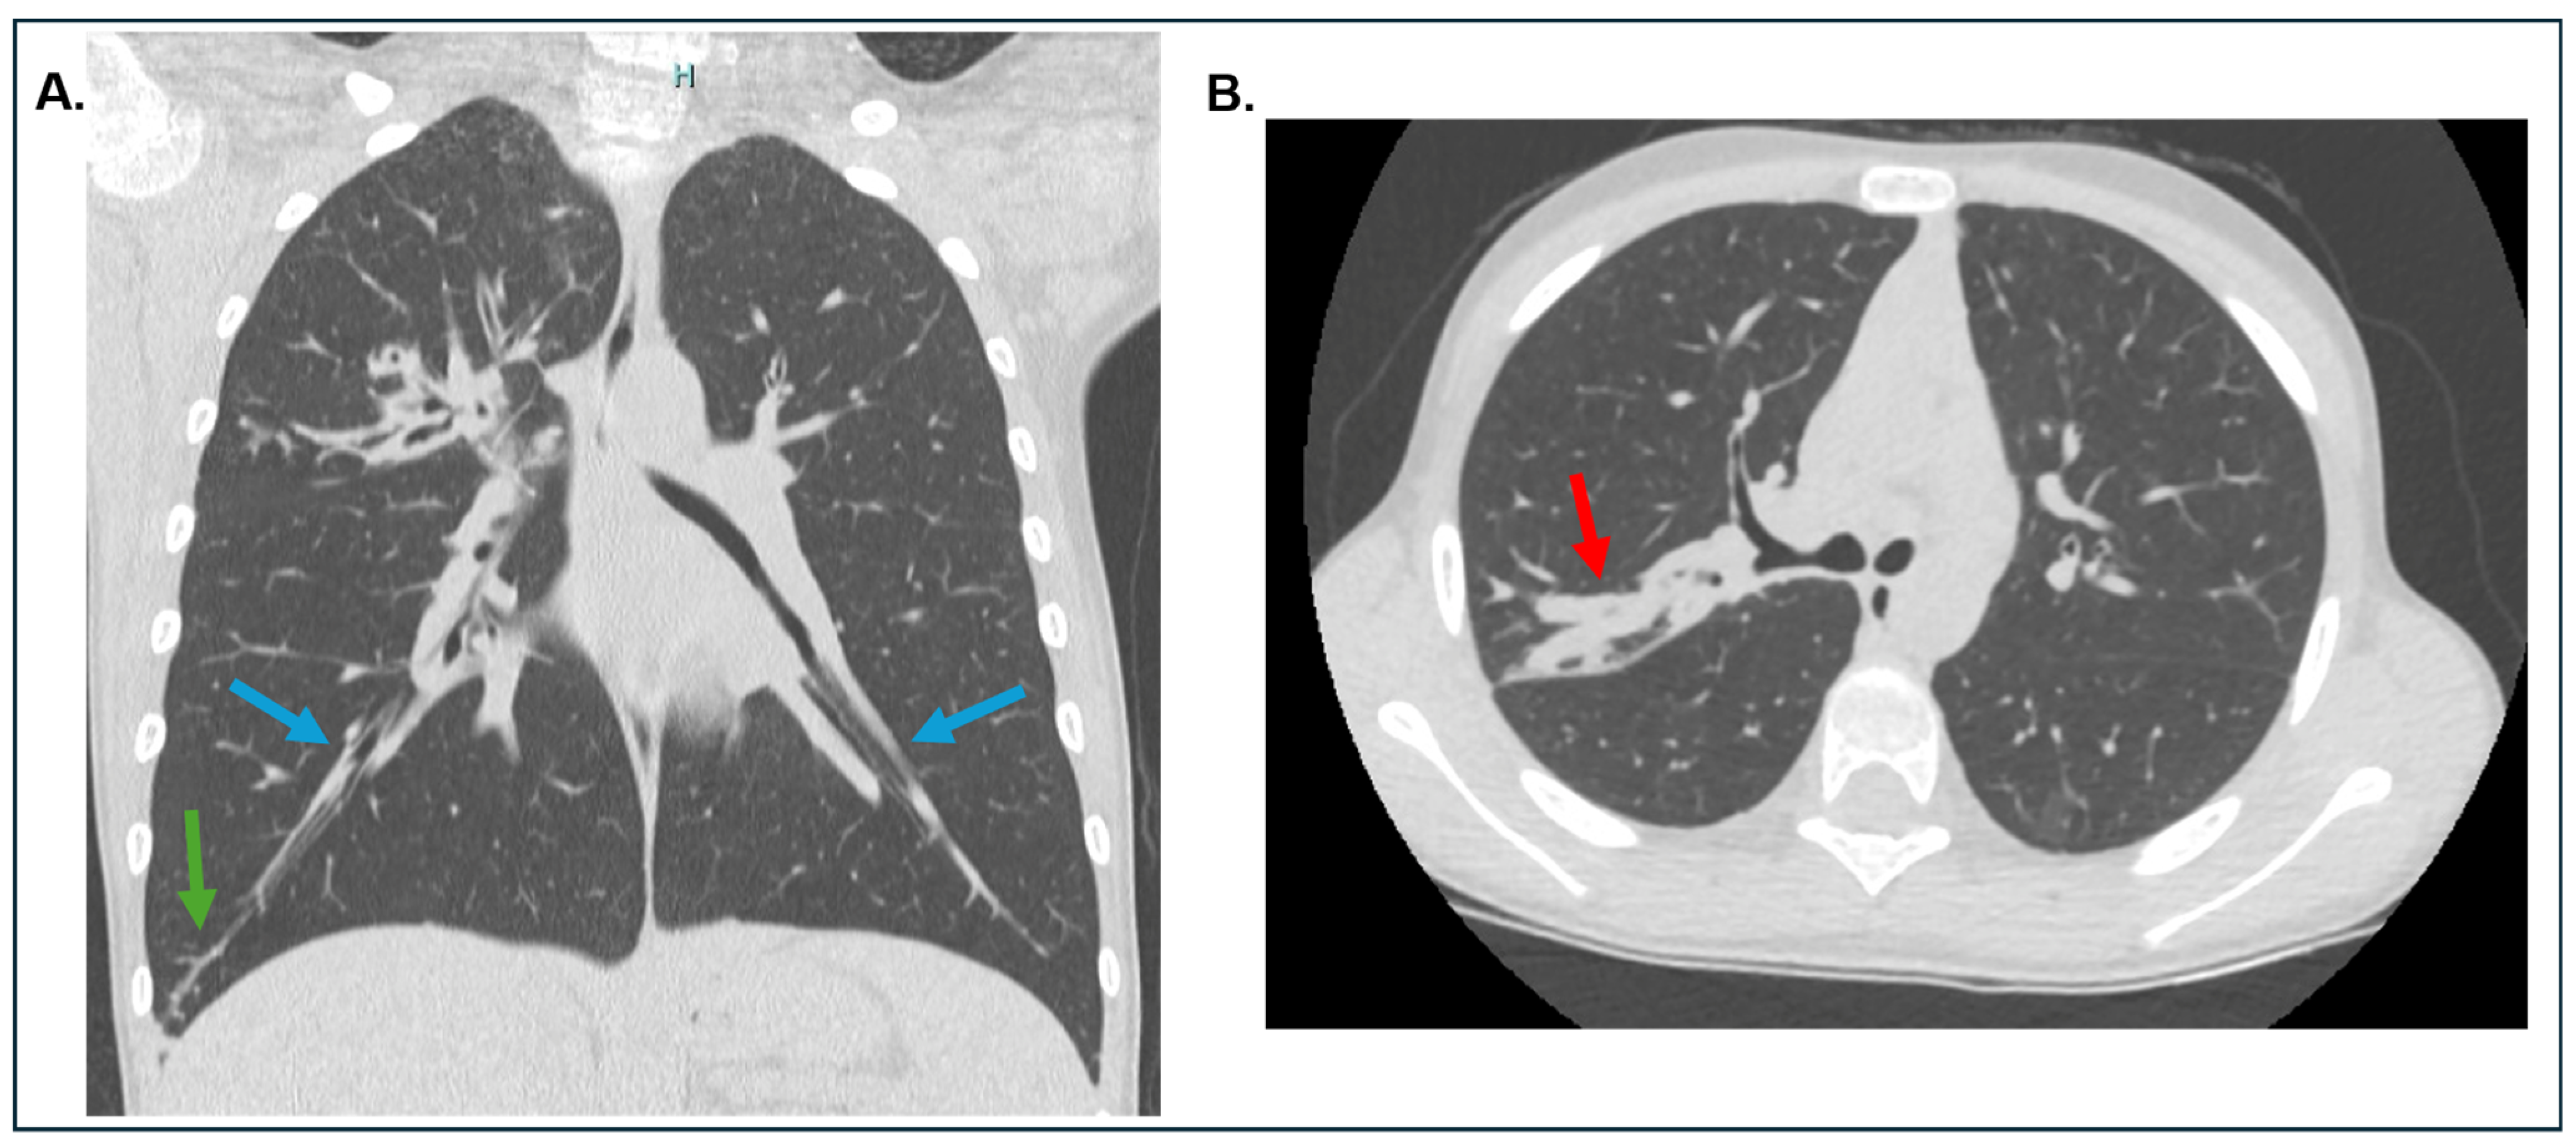

| 2. Serum total IgE > 500 IU/mL | 2. Bronchiectasis on CT chest scan | |